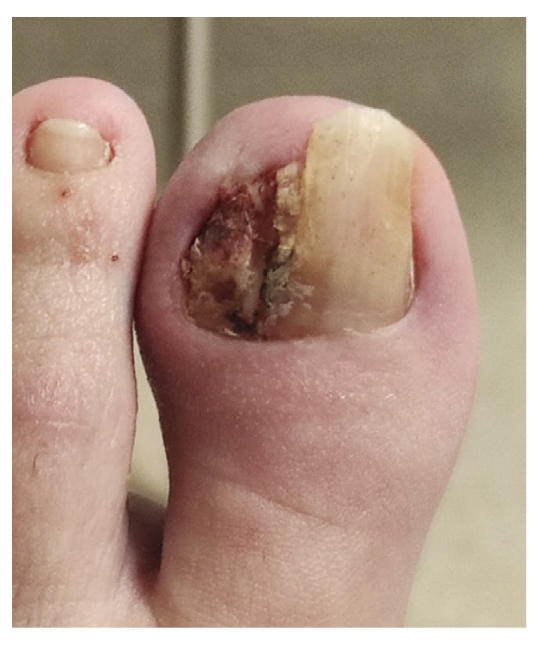

Tras empeoramiento del cuadro clínico, el 14 de noviembre de 2022 se realiza en su centro de salud la retirada parcial de la placa ungueal lateral del pie izquierdo junto con raspado, retirando tejido hiperqueratósico y de granulación. El procedimiento es repetido 48 h más tarde (16 de noviembre de 2022) por no haber retirado toda la lesión (Figura 3), cambiando el tratamiento antibiótico a anaclosil 500 mg 1/6 h y posteriormente a ciprofloxacino 500 mg 1/12 h durante las siguientes semanas.

Figura 3. Semana 8. Resección parcial de tejido hiperplásico realizado en su centro de salud.